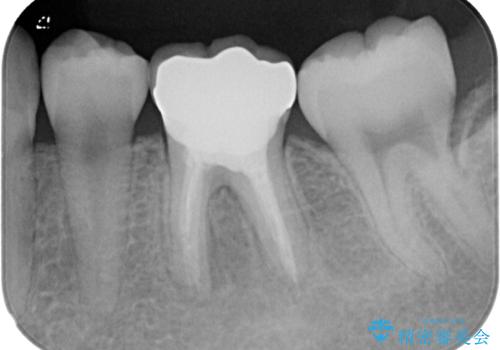

奥歯も著しく茶色に変色していたため、同様にオールセラミッククラウンにて補綴治療を行うこととしました。

明るく自然な口元になりました。